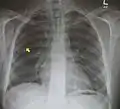

استرواح المنصف غير شائع ويحدث عندما يتسرب الهواء إلى المنصف يمكن تأكيد التشخيص عن طريق تصوير الأشعة السينية على الصدر والتي تبين صورةً إشعاعيةً حول القلب والمنصف أو عن طريق التصوير المقطعي للصدر.

استرواح المنصف مع علامة جناح الملاك